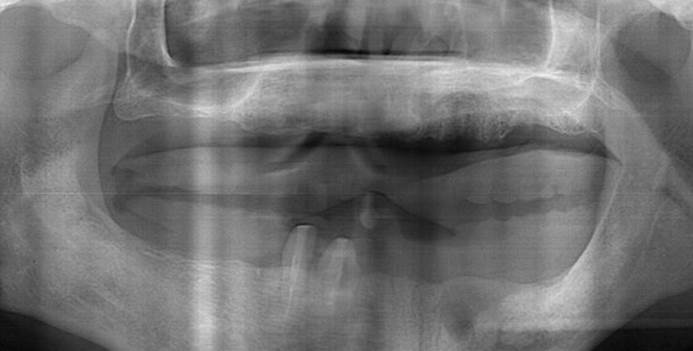

Clinical case: A Full transition from natural teeth to all-on-6 bridges

with AnyRidge implants

- Courtesy of Dr. Rabih Abi Nader, UAE -